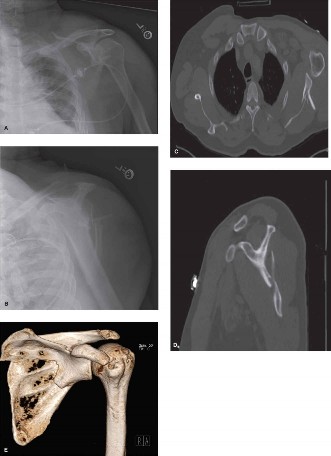

- Standard Radiographs: Anteroposterior (AP), Y-view (scapular lateral), and axillary views are initial staples. These help characterize the basic fracture pattern and assess displacement.

Computed Tomography (CT) Scan:

This is indispensable.

CT with 3D reconstructions (including coronal, sagittal, and axial cuts) provides the most comprehensive evaluation of the fracture morphology, articular involvement, displacement, angulation, and comminution. It is critical for glenoid fractures (Ideberg classification) and for identifying associated fractures not evident on plain radiographs.

- Figure 1: Pre-operative CT scan with 3D reconstruction demonstrating a complex scapular body and neck fracture with significant displacement and angulation. Such detailed imaging is critical for accurate surgical planning and identifying the optimal approach.